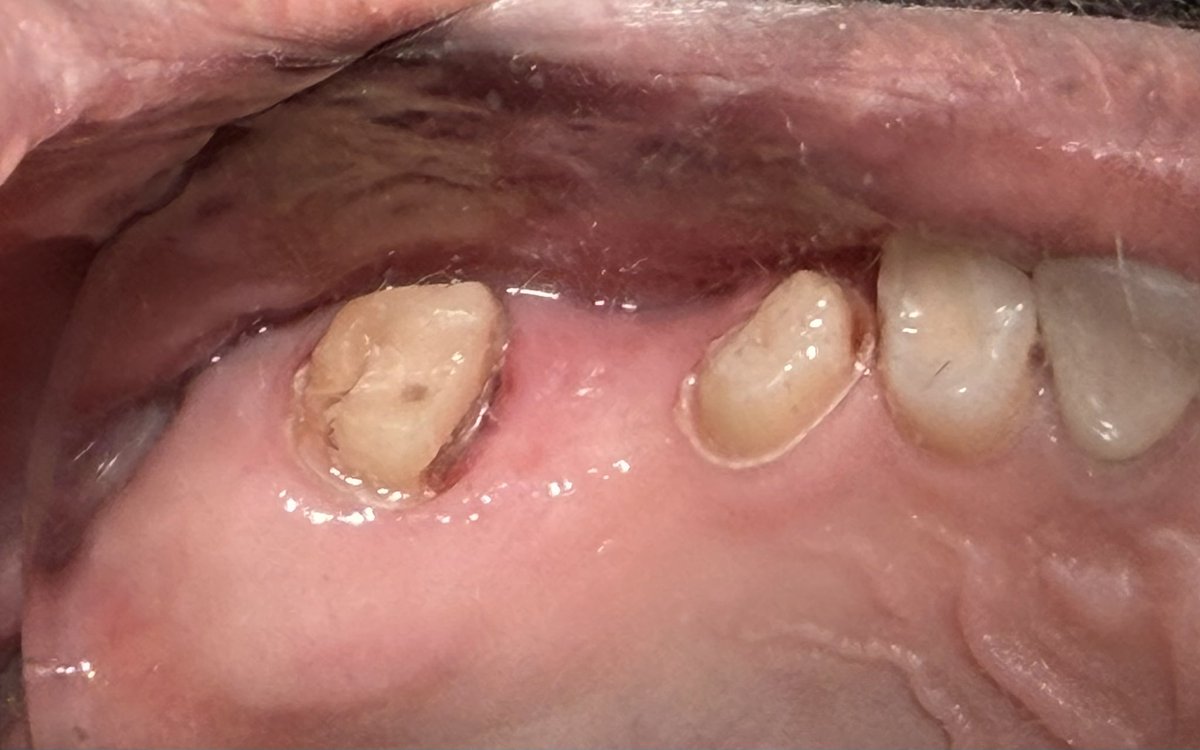

Today’s case✨: Replacement of missing #26 was accomplished using a zirconia fixed bridge (Shade B2). Tooth #27, previously endodontically treated, was reinforced with a fiber post and core build-up. Ensuring functional stability and optimal esthetics.